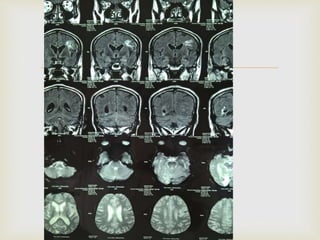

 At that time provisional diagnosis was mid brain

 The images MRI Brain showed

 On 2015 jan CVA with slurring of speech and right

  At thattime provisional diagnosis was mid brain stroke.  The images MRI Brain showed

  On 2015jan CVA with slurring of speech and right facial palsy. At that time CT brain was took